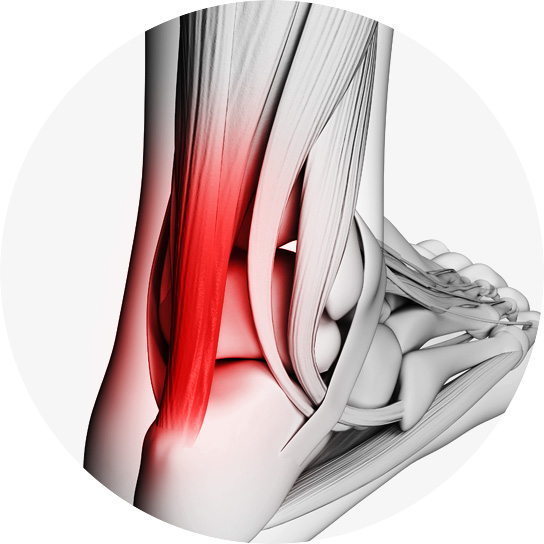

발뒤꿈치 뼈와 종아리 근육을 연결하는 아킬레스건에

발생하는 건병증입니다.

아킬레스건은 우리 몸에서 가장 크고 강력한 힘줄 중 하나이며,

걷기, 뛰기, 점프 등의 동작을 수행할 때 중요한 역할을 합니다.

아킬레스건염은 과도한 사용, 부적절한 운동, 잘못된 신발 착용

등으로 인해 발생할 수 있습니다.